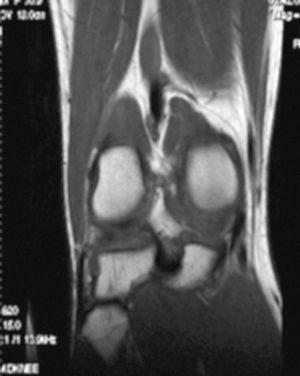

La RM muestra (figs. 1, 3 y 5):

Figura 1 RM. Imagen potenciada en T2 con supresión de grasa. Cuerpos libres en receso articular interno.

• Múltiples cuerpos libres intraarticulares.

• Lesión condral amplia en faceta externa y cresta de rótula, de grosor parcial.

• Derrame articular.

• Ligamentos y meniscos y resto de estructuras íntegras.